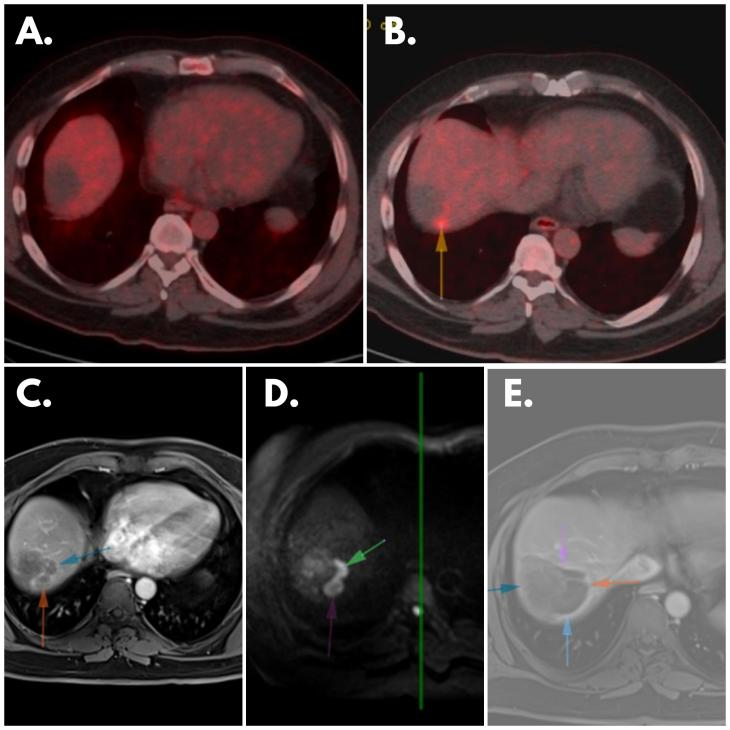

图2 患者扫描结果

(A) 2023年2月PET扫描:在低密度病灶区域未观察到显著的FDG积聚,表明缺乏代谢活性。(B) 2023年5月PET扫描:在先前确定的病灶后上方的紧邻区域出现新发的FDG摄取灶(箭头所示),提示代谢活性发生变化,表明疾病进展。(C) 2023年5月MR扫描:在2023年2月PET扫描描述的位置可见周边对比增强的病灶,表明血管增生增强。(D) 2023年5月MR扫描:在同一位置观察到弥散受限的病灶,表明病灶内水分弥散受限,可能是细胞密度增大和肿瘤活性增强的潜在标志。(E) 治疗后MRI:肺部出现无对比增强和弥散受限的空腔区域,提示治疗引起的变化,如坏死或先前确定病灶的消退,表明该特定解剖区域的治疗反应良好。